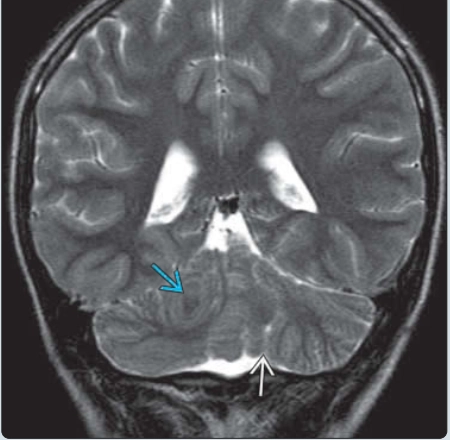

• Bất thường não sau

• DỊ TẬT DANDY-WALKER (DANDY-WALKER CONTINUUM)

• TẬT DÍNH TRÁM NÃO (RHOMBENCEPHALOSYNAPSIS)

• LOẠN SẢN TIỂU NÃO KHÔNG PHÂN LOẠI (UNCLASSIFIED CEREBELLAR DYSPLASIA)

• CÁC RỐI LOẠN LIÊN QUAN ĐẾN HỘI CHỨNG JOUBERT (JOUBERT SYNDROME RELATED DISORDERS - JSRD)

• THIỂU SẢN TIỂU NÃO (CEREBELLAR HYPOPLASIA)